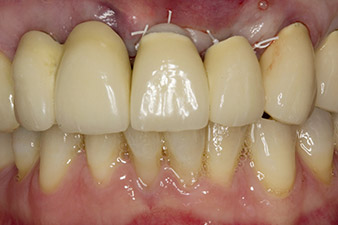

Alla prima visita, il paziente si presentava con ricostruzione su denti 21, 22 e 23 eseguita mediante corone splintate, ormai 19 anni prima, fissate agli impianti con attacchi in corrispondenza delle posizioni 12/11 (cfr. Fig. 2).

Dopo la prima guarigione, i tessuti molli sono stati sagomati con un ponte rivestito nella porzione basale. Due mesi dopo, il sito è stato esposto con una leggera incisione sula cresta palatoalveolare (Fig. 2). Si è visto che le dimensioni dell'osso alveolare erano sufficienti in corrispondenza della posizione 22. Le figure 2 e 4 mostrano la preparazione della sede di impianto, l'avvitamento e l'impianto utilizzando Implantmed.

In questo studio del caso la situazione è stata risolta con un impianto in corrispondenza della posizione 22 nella prima procedura, e con un impianto aggiuntivo in corrispondenza del dente estratto 23 nel corso del trattamento continuato. Il secondo impianto è stato inserito dopo che l'osteointegrazione dell'impianto 22 era avvenuta con successo. Il ponte modificato è stato reinserito fino a che l'impianto 23 era guarito e la sede era pronta per la ricostruzione definitiva. I vantaggi di questo approccio graduale includono la capacità dell'impianto di accettare carichi con più resilienza e i tessuti molli e duri più maturi (5).